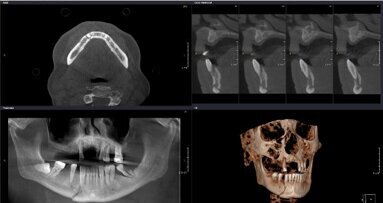

LEIPZIG, Germany: Cone-beam computed tomography (CBCT) has taken on greater significance over the past few years and has improved the standard of dental ...